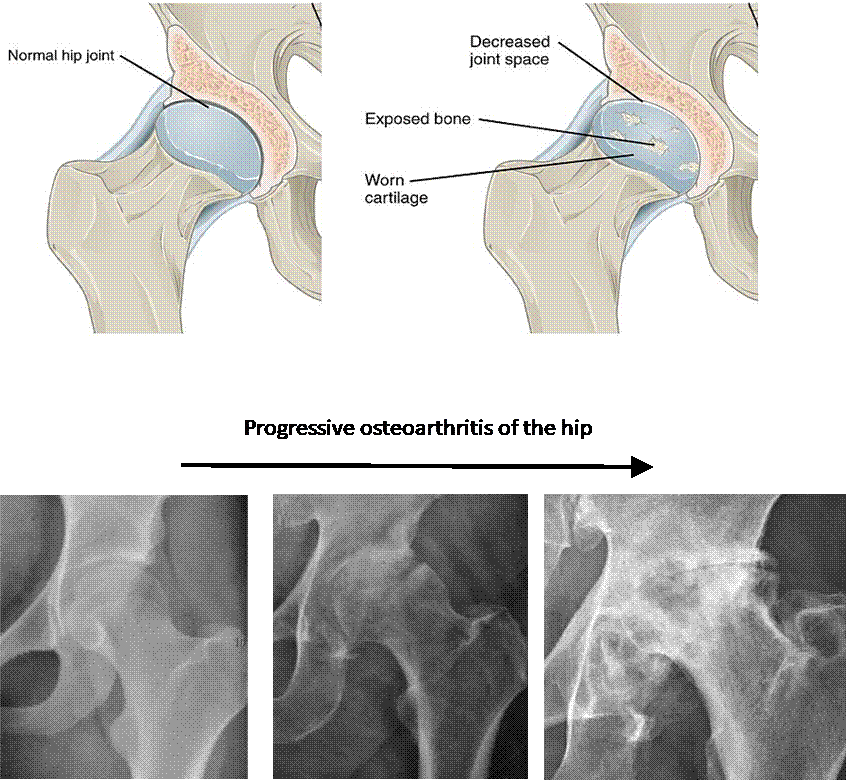

Fig. 9.10 Osteoarthritis. (Sources of images

and videos below. Used with permission.)

Note: (1) the progressive roughening of the round ball and its socket,

(2) the decreasing clear space (cartilage and fluid) between them,

(3) and the extra rough bone (white material) around the joint.

Description English:

Osteoarthritis in the hip. This is an edited version of the source

image made for use in the "Anatomist" iOS and Android app and shared

here under the terms of the source image's Share Alike Creative Commons

license.